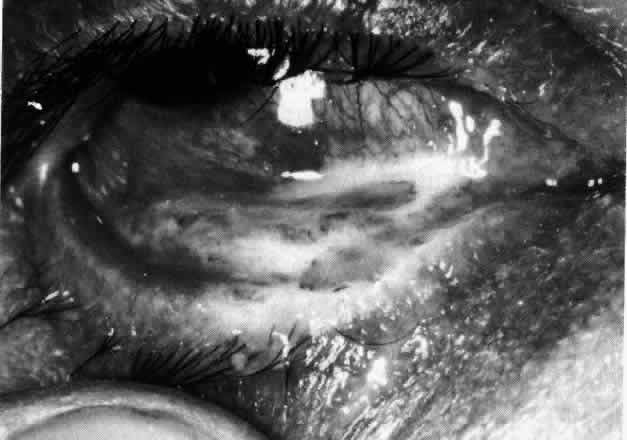

The redness of simple episcleritis may be intense, varying from a fiery-red or a brick-red discoloration to a mild red flush, but it does not have the bluish tinge that is seen in scleritis. The distribution is usually sectorial but can involve the whole anterior segment of the globe. The episcleral vessels are engorged but retain their normal radial position and architecture (Figs. 13 and 14; Color Plate 1A). In simple episcleritis, there is a diffuse edema of the episcleral tissues. These tissues are sometimes infiltrated with gray deposits that appear yellow in red-free light. Surprisingly, the eye is rarely tender to the touch.

Fig. 13. Infiltration of the episclera in which the superficial episcleral vessels show maximal congestion. Conjunctival vessels are slightly congested, as is the deep episcleral plexus, whose irregular criss-cross pattern can be seen deep to the radially arranged superficial episcleral plexus.

Fig. 14. Diffuse inflammation. Superficial vessels are maximally engorged and retain their radial pattern and architecture. (See Figures 27 and 34.) (Watson PG: Connective tissue disorders and the eye. In: Recent Advances in Ophthalmology, Vol 5, pp 214–277. London, Churchill-Livingstone, 1975)